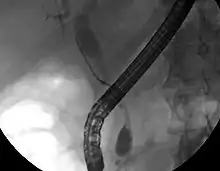

ERCP image of cholangiocarcinoma, showing common bile duct stricture and dilation of the proximal common bile duct

While abdominal imaging can be useful in the diagnosis of cholangiocarcinoma, direct imaging of the bile ducts is often necessary. Endoscopic retrograde cholangiopancreatography (ERCP), an endoscopic procedure performed by a gastroenterologist or specially trained surgeon, has been widely used for this purpose. Although ERCP is an invasive procedure with attendant risks, its advantages include the ability to obtain biopsies and to place stents or perform other interventions to relieve biliary obstruction.[12] Endoscopic ultrasound can also be performed at the time of ERCP and may increase the accuracy of the biopsy and yield information on lymph node invasion and operability.[55] As an alternative to ERCP, percutaneous transhepatic cholangiography (PTC) may be utilized. Magnetic resonance cholangiopancreatography (MRCP) is a non-invasive alternative to ERCP.[56][57][58] Some authors have suggested that MRCP should supplant ERCP in the diagnosis of biliary cancers, as it may more accurately define the tumor and avoids the risks of ERCP.[59][60][61]